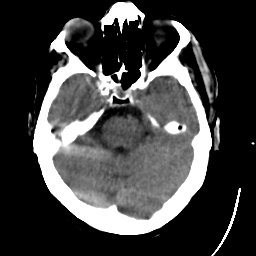

Meningioma: Roentgen-ray CT #1 -- Slice #6

[Home][Help][Clinical] Slice 6